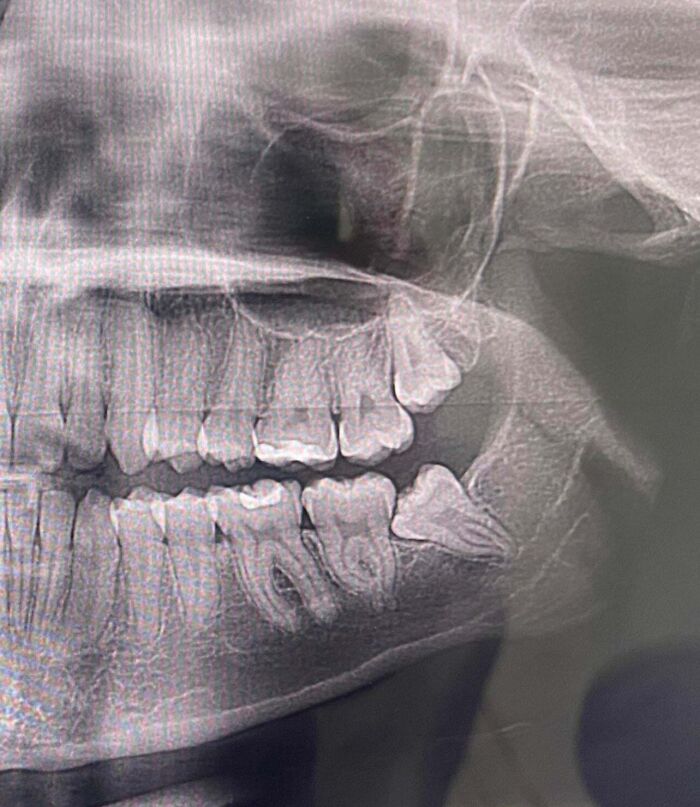

Dentist Office Charged My Sister $500 For A CT Scan They Never Performed

Went in today to see the apparent CT scan taken last week compared to the current X-rays. The “current” CT scan is missing her implant that was put in 5 years ago…